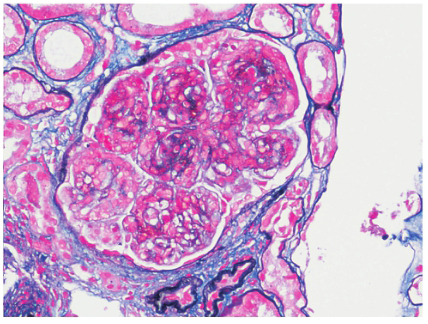

肾活检示免疫荧光:C3(+++),余阴性,系膜区、毛细血管壁颗粒样沉积(图1)。光镜下可见24个肾小球,肾小球系膜细胞和基质中重度弥漫增生,广泛插入,基底膜增厚,双轨征形成,系膜区、内皮下嗜复红蛋白沉积;肾小管上皮空泡及颗粒变性,灶状萎缩;肾间质灶状淋巴和单核细胞浸润伴纤维化;小动脉管壁增厚;符合膜增生性肾小球肾炎(MPGN)(图2)。电镜下肾小球系膜细胞和基质中度增生,广泛插入,基底膜增厚,上皮下、基底膜内、内皮下、系膜区均可见电子致密物沉积,上皮足突广泛融合(图3);符合MPGN。结合患者免疫荧光结果,最终诊断为C3肾小球肾炎。

图2 MPGN型C3肾小球肾炎:肾小球系膜细胞增生和系膜基质增多,毛细血管壁增厚,双轨征形成(PASM+Masson×200)